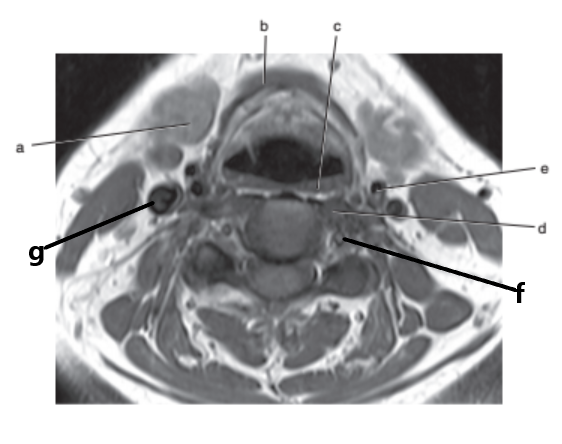

What imaging plane is this ?

transverse

Parotid gland

Masseter muscle

What is letter e ?

Epiglottis

What is letter d ?

Soft palate

Mandible